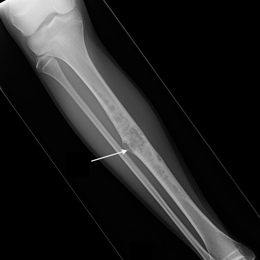

Radiographic imaging is used to help form a diagnosis of ABC. These include X-Ray, MRI, CT and Bone Scans.

An example of an Adamantinoma X-Ray is shown.

Radiographic Image of an Adamantinoma

On an X-Ray, also called a radiograph, an adamantinoma can be diagnosed by looking at certain features. Most commonly seen in adamantinoma is a sharply defined osteolytic defect which is lobulated, multicystic, or a “soap bubble”.